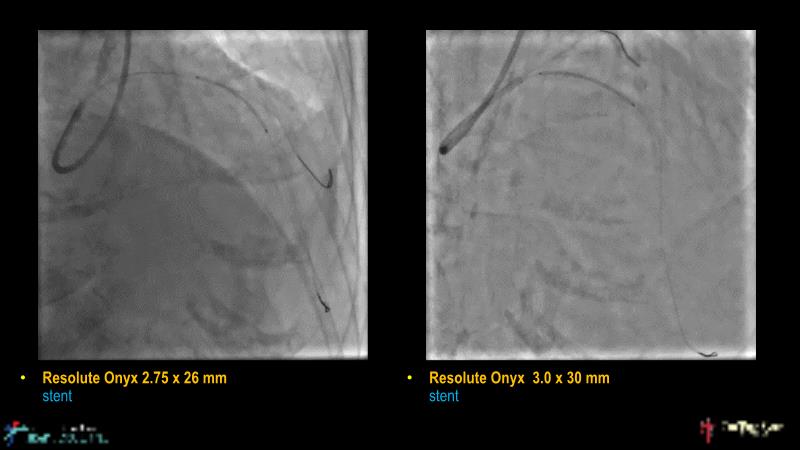

Watch this case-based session to follow discussion about how to choose between DES & DCB, how both can be complementary in diffuse disease as well as in complex PCI, and how physiology and imaging can help guiding PCI, and follow a patient's treatment live.

- To learn the tips and tricks in performing complex PCI intervention with DES and/or DCB

- To discuss cases when DES and DCB are complementary

- To discover strategies to simplify complex PCI cases with the latest DES and DCB